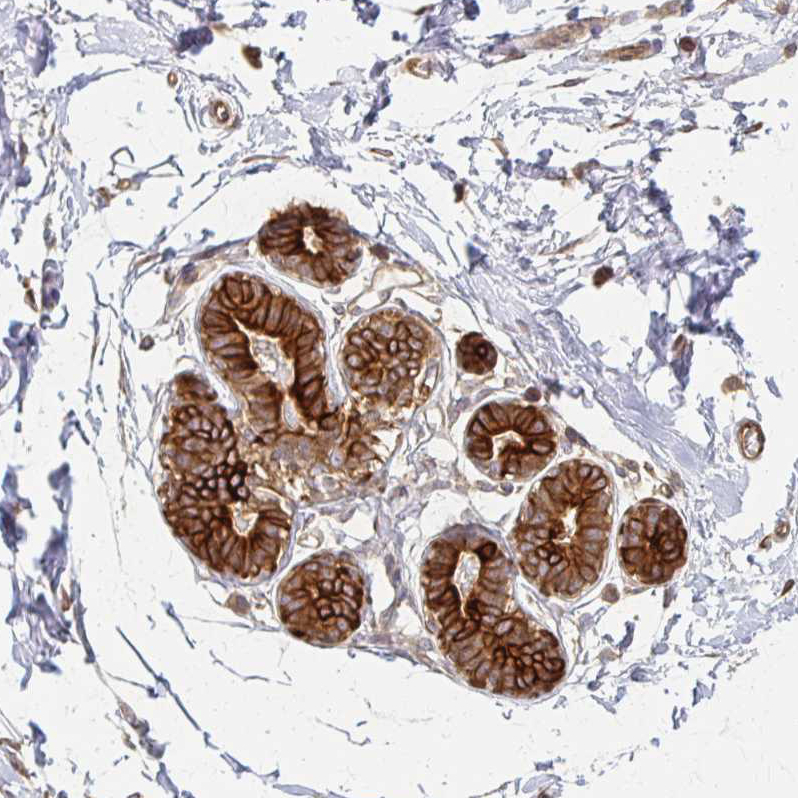

Immunohistochemical staining of human breast shows strong membranous and cytoplsmic positivity in glandular cells.